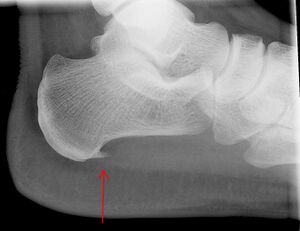

عظم العقب ومهماز العقب (السهم الأحمر)

النتيجة العرضية المرتبطة بهذه الحالة هي مهماز العقب، تكلس عظمي صغير على العقب (عظم الكعب)، الذي يتواجد في حوالي إلى 50٪ من المصابين بالتهاب اللفافة الأخمصية.[6] في مثل هذه الحالات، فإن التهاب اللفافة الأخمصية هو الذي يسبب ألم العقب، وليس المهماز نفسه.[13] الحالة هي المسؤولة عن تكوين المهماز على الرغم من أن الأهمية السريرية لمهماز العقب في التهاب اللفافة الأخمصية لا تزال غير واضحة.[12]

لا توجد حاجة روتينية للتصوير الطبي. فهو مكلف ولا يغير عادة كيفية علاج التهاب اللفافة الأخمصية.[15] عندما لا يكون التشخيص واضحًا من الناحية السريرية، فإن الأشعة السينية للرؤية الجانبية للكاحل هي طريقة التصوير الموصى بها لتقييم الأسباب الأخرى لألم الكعب، مثل كسور الإجهاد أو تطور مهماز العقب.[7]